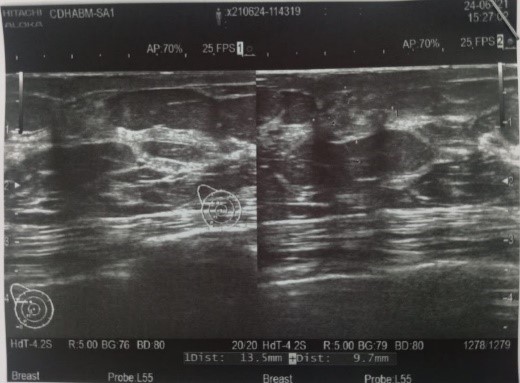

![]() |

Hình ảnh siêu âm và nhũ ảnh của bệnh nhân Vũ Thị M, 60t